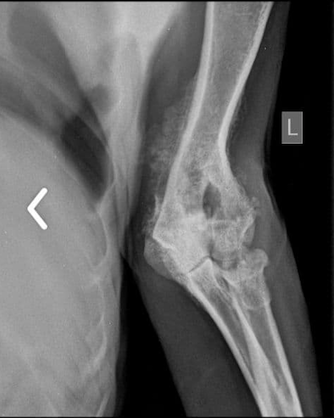

Рентгеновский снимок травмы лапы у Тихона.

В марте 2021 года поддерживаемая нами финансово (оплата передержек, корма, медицинских препаратов) и информационно Минская группа волонтеров забрала из минской "усыпалки" (печально известной "Фауны города" на Гурского, 42) трех собак – старого гончака Тихона (после того, как он начал хромать из-за застарелого сросшегося перелома, хозяева сдали для усыпления), щенков Весту и Нику.

После санитарной обработки и прививок для Весты и Ники уже нашли хозяев, а Тихона после медобследования, анализов, включая сдачу крови и УЗИ (врач не рекомендовал хирургического вмешательства из-за преклонного возраста собаки), прописывания медикаментов от увеличенной вследствие возраста печени и кастрации взяли на кураторство и платную передержку (около 75 долларов в месяц) с хорошим кормом (около 60-80 долларов в месяц) и регулярным выгулом (с оплатой бензина для приезжающего выгуливать волонтера) в поддерживаемой нами Минской группе волонтеров.